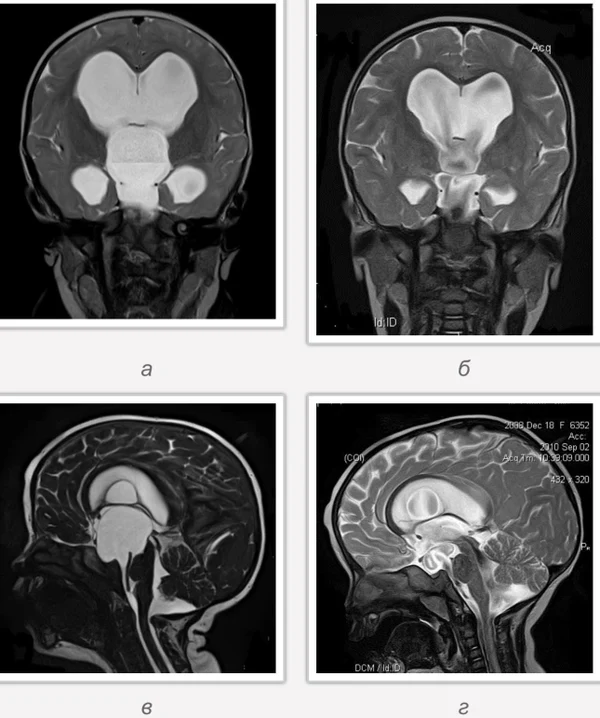

кисты, аномалии Денди-Уокера и др.Операции при внутричерепных кистах. В основном встречаются арахноидальные кисты различных локализаций и кисты сосудистых сплетений боковых желудочков. Пациентам с врождёнными кистами операции проводятся в следующих ситуациях: увеличении объема кисты в динамике, наличии клинических проявлений, компрессии и дислокации мозговых структур, наличии окклюзии ликворных путей. Нами используются 2 способа хирургического лечения кист: эндоскопическая перфорация стенок кист и открытая резекция кист. Открытая резекция кист проводится при ретроцеребеллярных арахноидальных кистах (рис. 2), при арахноидальных кистах межполушарной щели при отсутствии непосредственного контакта их стенок со стенками расширенных желудочков головного мозга и повторного увеличения кист средней черепной ямки после эндоскопической кисто-цистерностомии. Техника операции заключается в проведение краниотомии и максимальном иссечении стенок кист с созданием широкого сообщения кист с субарахноидальным пространством. Эндоскопические операции проводятся при арахноидальных кистах межножковой и пинеальной цистерн, арахноидальных кистах межполушарной щели при тесном контакте их стенок со стенками расширенной желудочковой системы (рис. 3), первично при арахноидальных кистах средней черепной ямки, а также при кистах сосудистых сплетений боковых желудочков. При арахноидальных кистах межножковой цистерны эндоскопически проводится перфорация стенок кисты, сообщая ее с просветом III желудочка и межножковой цистерной – эндоскопическая вентрикуло-кисто-цистерностомия (рис. 4). При арахноидальных кистах пинеальной цистерны проводится перфорация кисты в передне-верхних её отделах с созданием сообщения полости кисты с просветом III желудочка – эндоскопическая кисто-вентрикулостомия. С целью предотвращения облитерации сформированного отверстия иногда в полость кисты под контролем эндоскопа вводится стент перфорированный на протяжении (рис. 5, 6). Эндоскопическая кисто-цистерностомия выполняется при арахноидальных кистах средней черепной ямки. При этом создается широкое сообщение кисты с базальными цистернами. При кистах сосудистых сплетений боковых желудочков проводится их вскрытие в просвет боковых желудочков – эндоскопическая кисто-вентрикулостомия. При множественных кистах проводится их хирургическое сообщение между собой – интеркистосмия